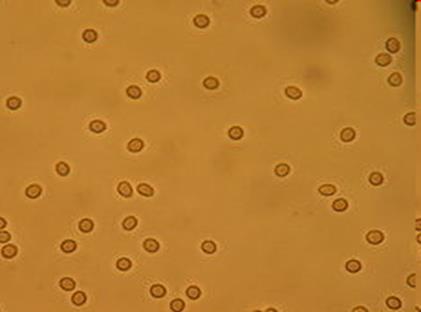

In medicine, hematuria, or haematuria, is the presence of red blood cells (erythrocytes) in the urine.